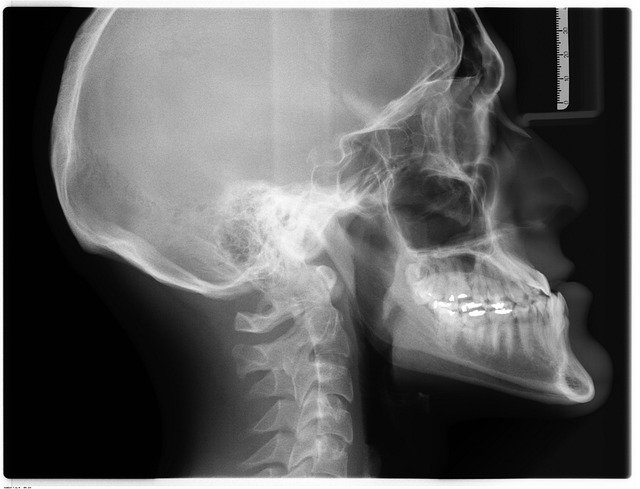

- Raios-X – Permite avaliar fraturas e outras anomalias em diversas partes do corpo. Os equipamentos de raios-X já têm recursos que permitem diminuir a exposição à radiação, pois é prejudicial à saúde.

- Tomografia Computorizada – Permite colher centenas de radiografias de uma área e os aparelhos mais modernos permitem que estas imagens se sobreponham, fornecendo um registo 3D.

- Densitometria Óssea – Com o uso do aparelho DEXA (Densitometria por Raios-X de energia dupla), o médico radiologista consegue captar imagens em corte dos ossos. É usado, por exemplo, para detetar osteoporose.